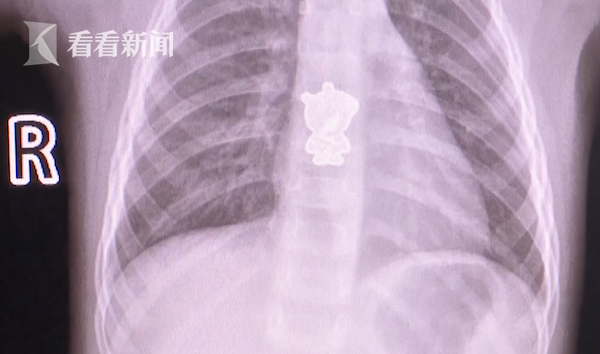

12月24日早上,湖南长沙一岁女童悦悦(化名)起床后一直哭闹不止,家长怎么也找不出原因,于是赶紧将其送往医院检查。医生通过CT检查发现,孩子体内竟藏了个“小猪佩奇”?

孩子母亲回忆,这个小猪佩奇应该是悦悦鞋子上的装饰,鞋子上装饰缝得也不怎么牢固,孩子可能看到好玩,就扣下来了。也不知道什么时候就塞进了嘴里。。。。。。

幸好,检查及时发现了异物,医生已经通过手术,取出了这个让孩子不停哭闹的“元凶”。